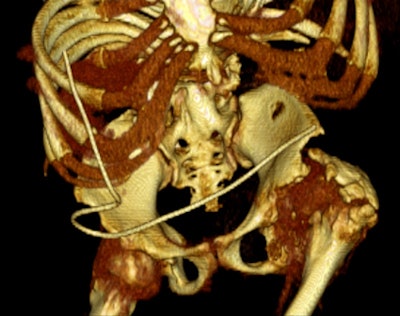

An 18-year-old female with "after-party amnesia" presented with severe stomach pain and bruises to the head. An investigation showed vaginal bleeding was from the bladder. Full-scale emergency room investigation showed severe left kidney fracture and contusion, but intact vessels and ureter. Three-month follow-up renography shows 28% kidney function on left side as the only sequelae. Image courtesy of Dr. Vibeke Logager.

Imaging should be part of good follow-up protocols, which also include clinical consultation and urodynamic assessment, he continued. All these are important to reduce long-term problems with bladder dysfunction, but certain prostheses can make imaging more difficult, such as spinal or other bony metal devices used for fixation of trauma or corrective spinal surgery for deformity. Prostheses associated with the urinary tract that may also cause imaging difficulties are neuromodulation devices, such as sacral nerve stimulators or artificial sphincters.